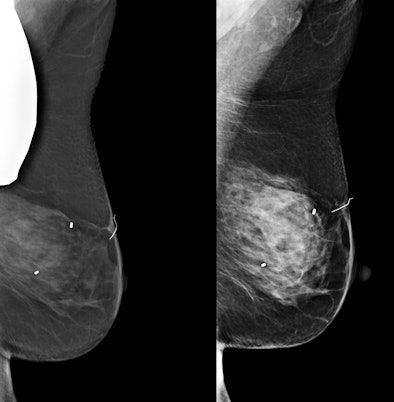

Images from a patient who underwent mammography with a thyroid shield. The image on the left is a mediolateral oblique view demonstrating the thyroid shield obscuring the upper posterior breast along with a degraded image. The image on the right was repeated without the shield and shows normal breast tissue. All images courtesy of Dr. Phil Evans.When Kopans commented to Oz that "if you are going to promote thyroid shields for mammograms, your audience should be wearing them now" to protect the thyroid gland from normal background radiation levels that cumulatively are much greater, Oz interrupted him. Oz stated that the protection was for a dose that a thyroid gland was receiving in one second rather than spread over 30 minutes, and why not protect oneself during that one second?

A technologist positioned for a mammogram with the thyroid shield in place. Part of the thyroid shield is underneath the compression paddle and would cause a portion of the breast to be obscured on the mammogram.